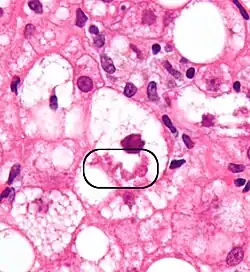

Микроскопическая характеристика

При окрашивании гематоксилином и эозином приобретают розовый цвет и хорошо различимы, однако, наилучший диагностический вариант — иммуногистохимическая окраска на убиквитин или цитокератины[1].

При микроскопии тельца Мэллори классифицируют следующим образом[1]:

- Тип I — параллельные филаменты;

- Тип II — беспорядочно ориентированные филаменты, встречающиеся по периферии клетки;

- Тип III — аморфные, располагаются вокруг центра клетки.